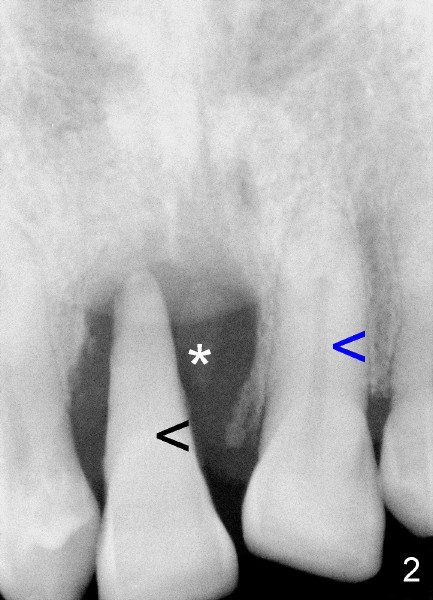

Sixty-one-year-old otherwise healthy man requests extraction of the upper right central incisor, which is mobile and supraerupted (Fig.1 arrow). He denies the history of trauma, although X-ray shows sclerosed canal of the affected tooth (Fig.2 black <, as compared to that of the left central (blue <).